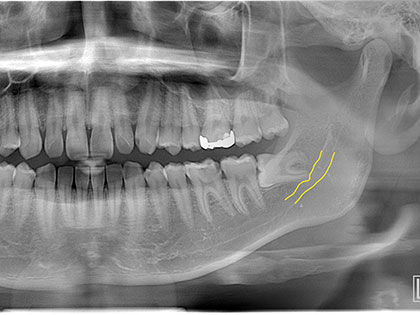

親知らず抜歯症例

親知らず抜歯症例9

右下親知らずを抜きたいとの事で来院、治療を希望された患者様の症例になります